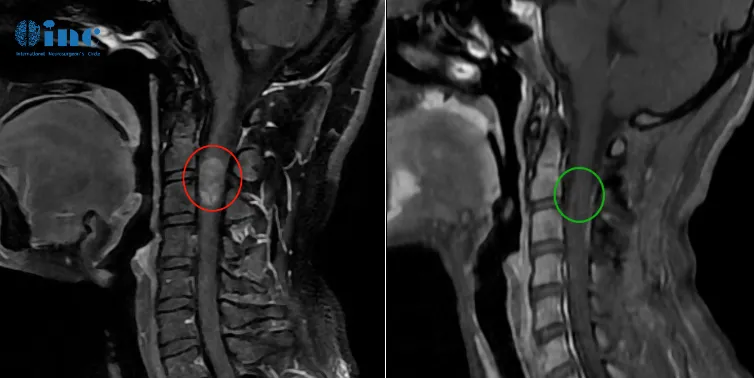

患者田田是一名21岁的在校女大学生,在一次参加完常规体育运动后自感后背轻微疼痛,两天后出现双下肢无力,检查诊断胸髓髓内出血性病变。

后续病情进展很快,还出现小便困难,双下肢无力加重等症状。再次检查后确诊胸髓髓内6海绵状血管瘤,医生考虑血管瘤位置比较深,在腹侧,手术风险大,做完肯定会瘫痪,建议保守治疗。再次出血,两天内症状急剧加重,双下肢运动功能丧失,大小便失禁。

2023年3月24日,在苏州大学附属四医院,巴教授顺利为田田顺利手术,术后无新发神经功能损伤。术后一天ICU查房田田意识清醒,交流正常。右腿伸直略微困难,脚趾活动正常。术后五天普通病房查房田田感觉很好,右腿活动正常,双腿肌力正常。术后两周情况目前田田术后两周,已经可以下床行走活动,术前的症状有所缓解。术后两个月时,田田正在稳定康复训练中。